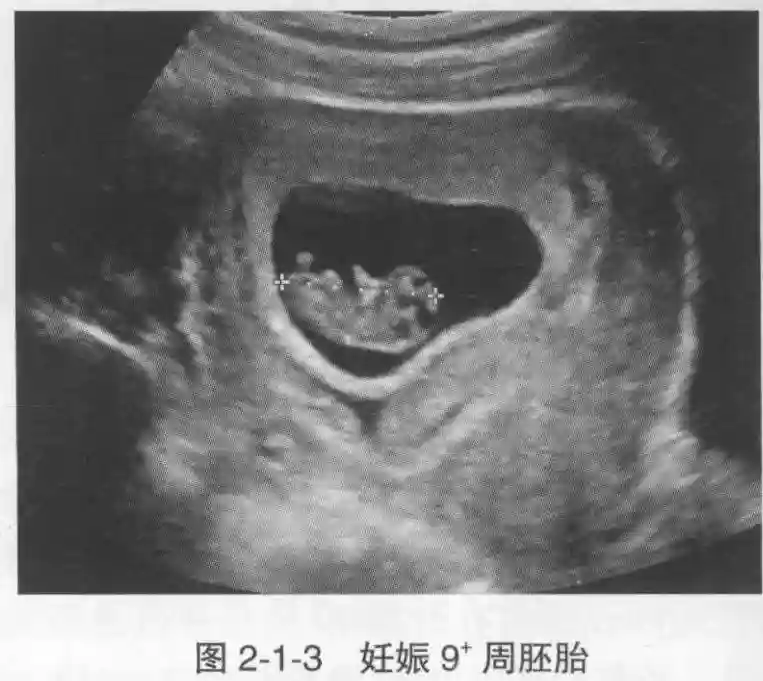

3️⃣胚胎:胚胎通常在6-7周时可以为超声显示,起初为胎芽,表现为卵黄囊一侧局部组织增厚,达到1 -2 mm 时才有可能为超声测量出来。达4-5mm时可见胎心搏动,相应孕周为6-6.5周,妊娠囊大小为13-18mm。胚芽长度≥7㎜时仍未见心管搏动,提示胚胎停止发育。胚胎的出现和妊娠囊直径的关系:妊娠囊直径> 16 mm 时,经阴道超声应显示胚胎。妊娠囊直径> 25 mm 时,经腹超声均应显示胚胎。